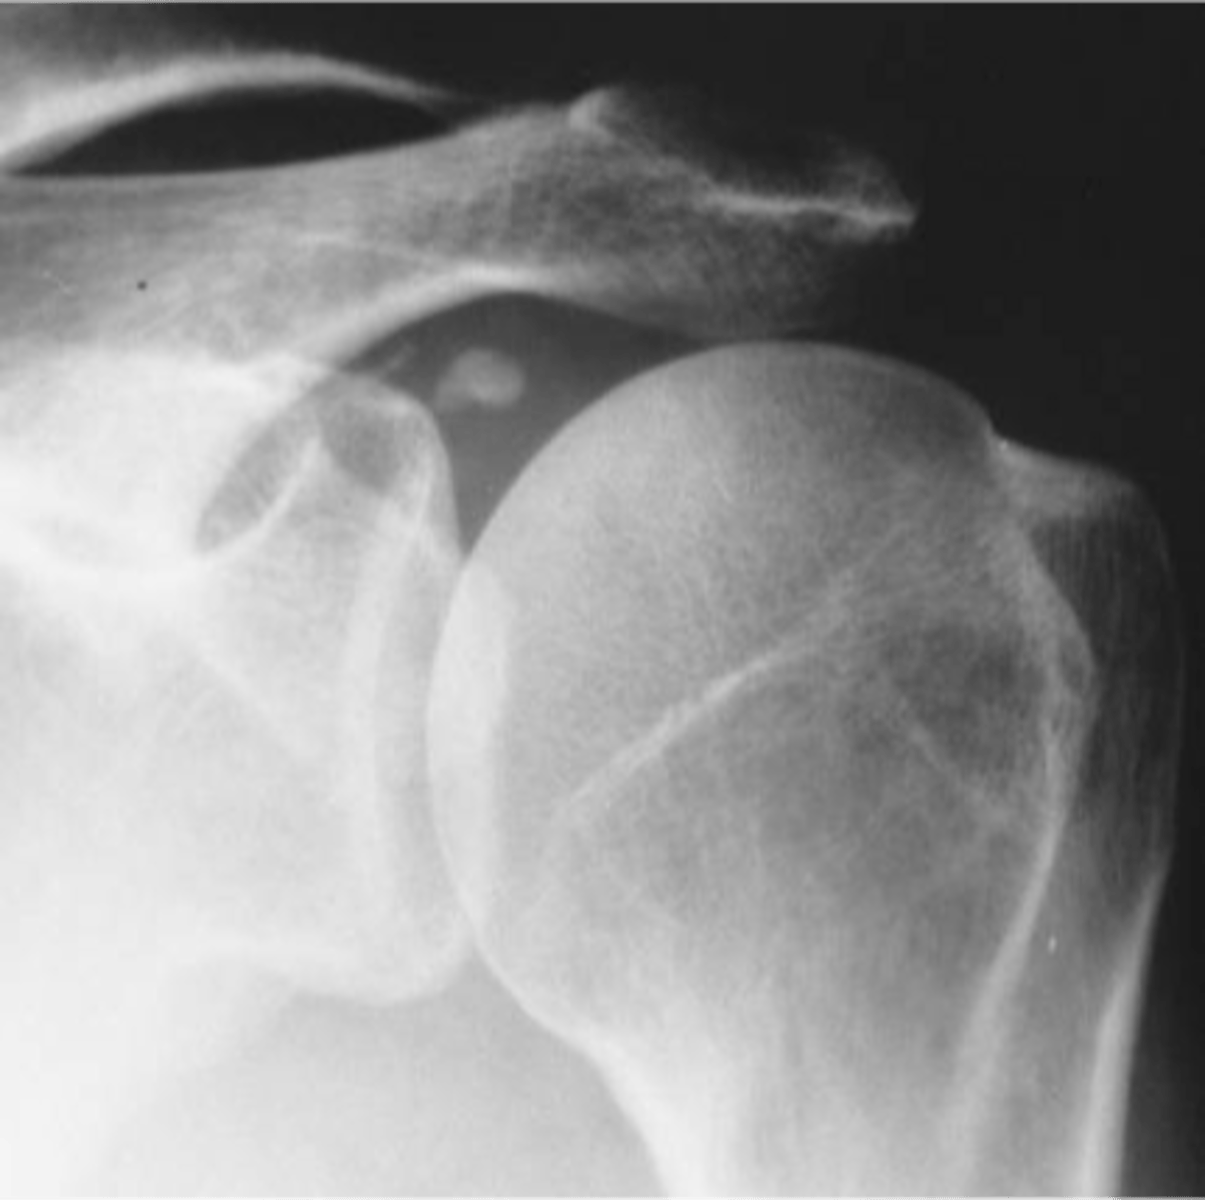

- Deposition of calcium hydroxyapatite within a tendon, bursa, or other periarticular soft tissue

- May cause tendinitis, bursitis, and joint pain

Calcific tendinitis

Another term for hydroxyapatite deposition disease (HADD)

Supraspinatus

Hydroxyapatite deposition disease (HADD) of the _____